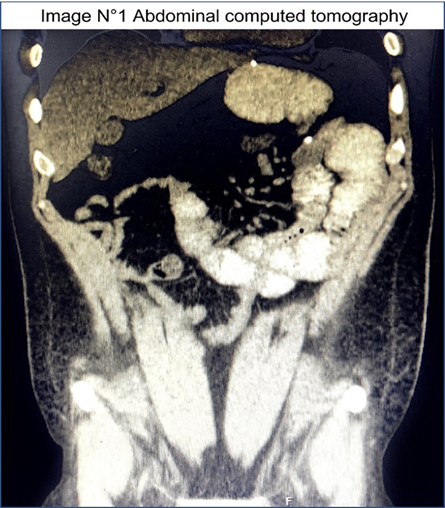

Open AccessCase Report

Roux-en-O Gastric Bypass. Treatment of a Severe Complication

Norberto Daniel Velasco Hernandez, Santiago B. De Battista, Lucas A. Rivaletto, Carolina Gómez Oro

International Journal of Innovative Research in Medical Science·December 1, 2022